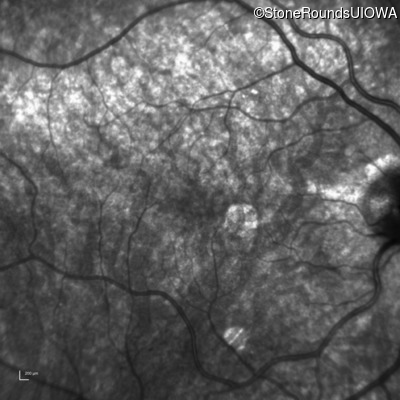

Infrared Fundus Photograph - Right - 20/20 sc

Exemplar